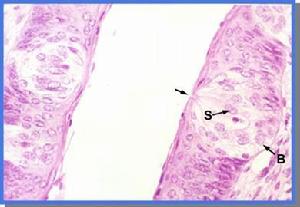

上皮含有感覺細胞(初生的、次生的),具有刺激的感受機能。是由上皮細胞特化...,因此感覺較靈敏。例如,皮膚的表皮和支氣管上皮就如此。細胞間連線在上皮細胞...分類被覆上皮 上皮組織整裝片 根據上皮細胞的排列層數和形狀,又將被覆...